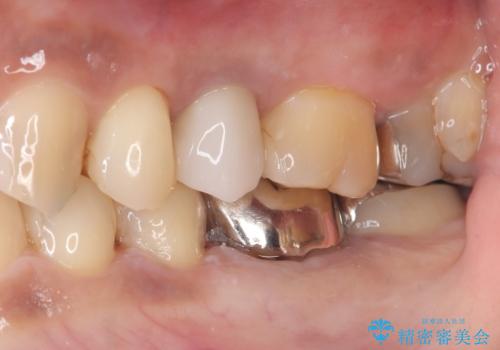

メタルインレーを除去したところ、二次カリエスうを確認したため除去・CR裏層の後、形成・印象しています。

セラミックインレーの接着操作時にはラバーダム防湿を行っています。